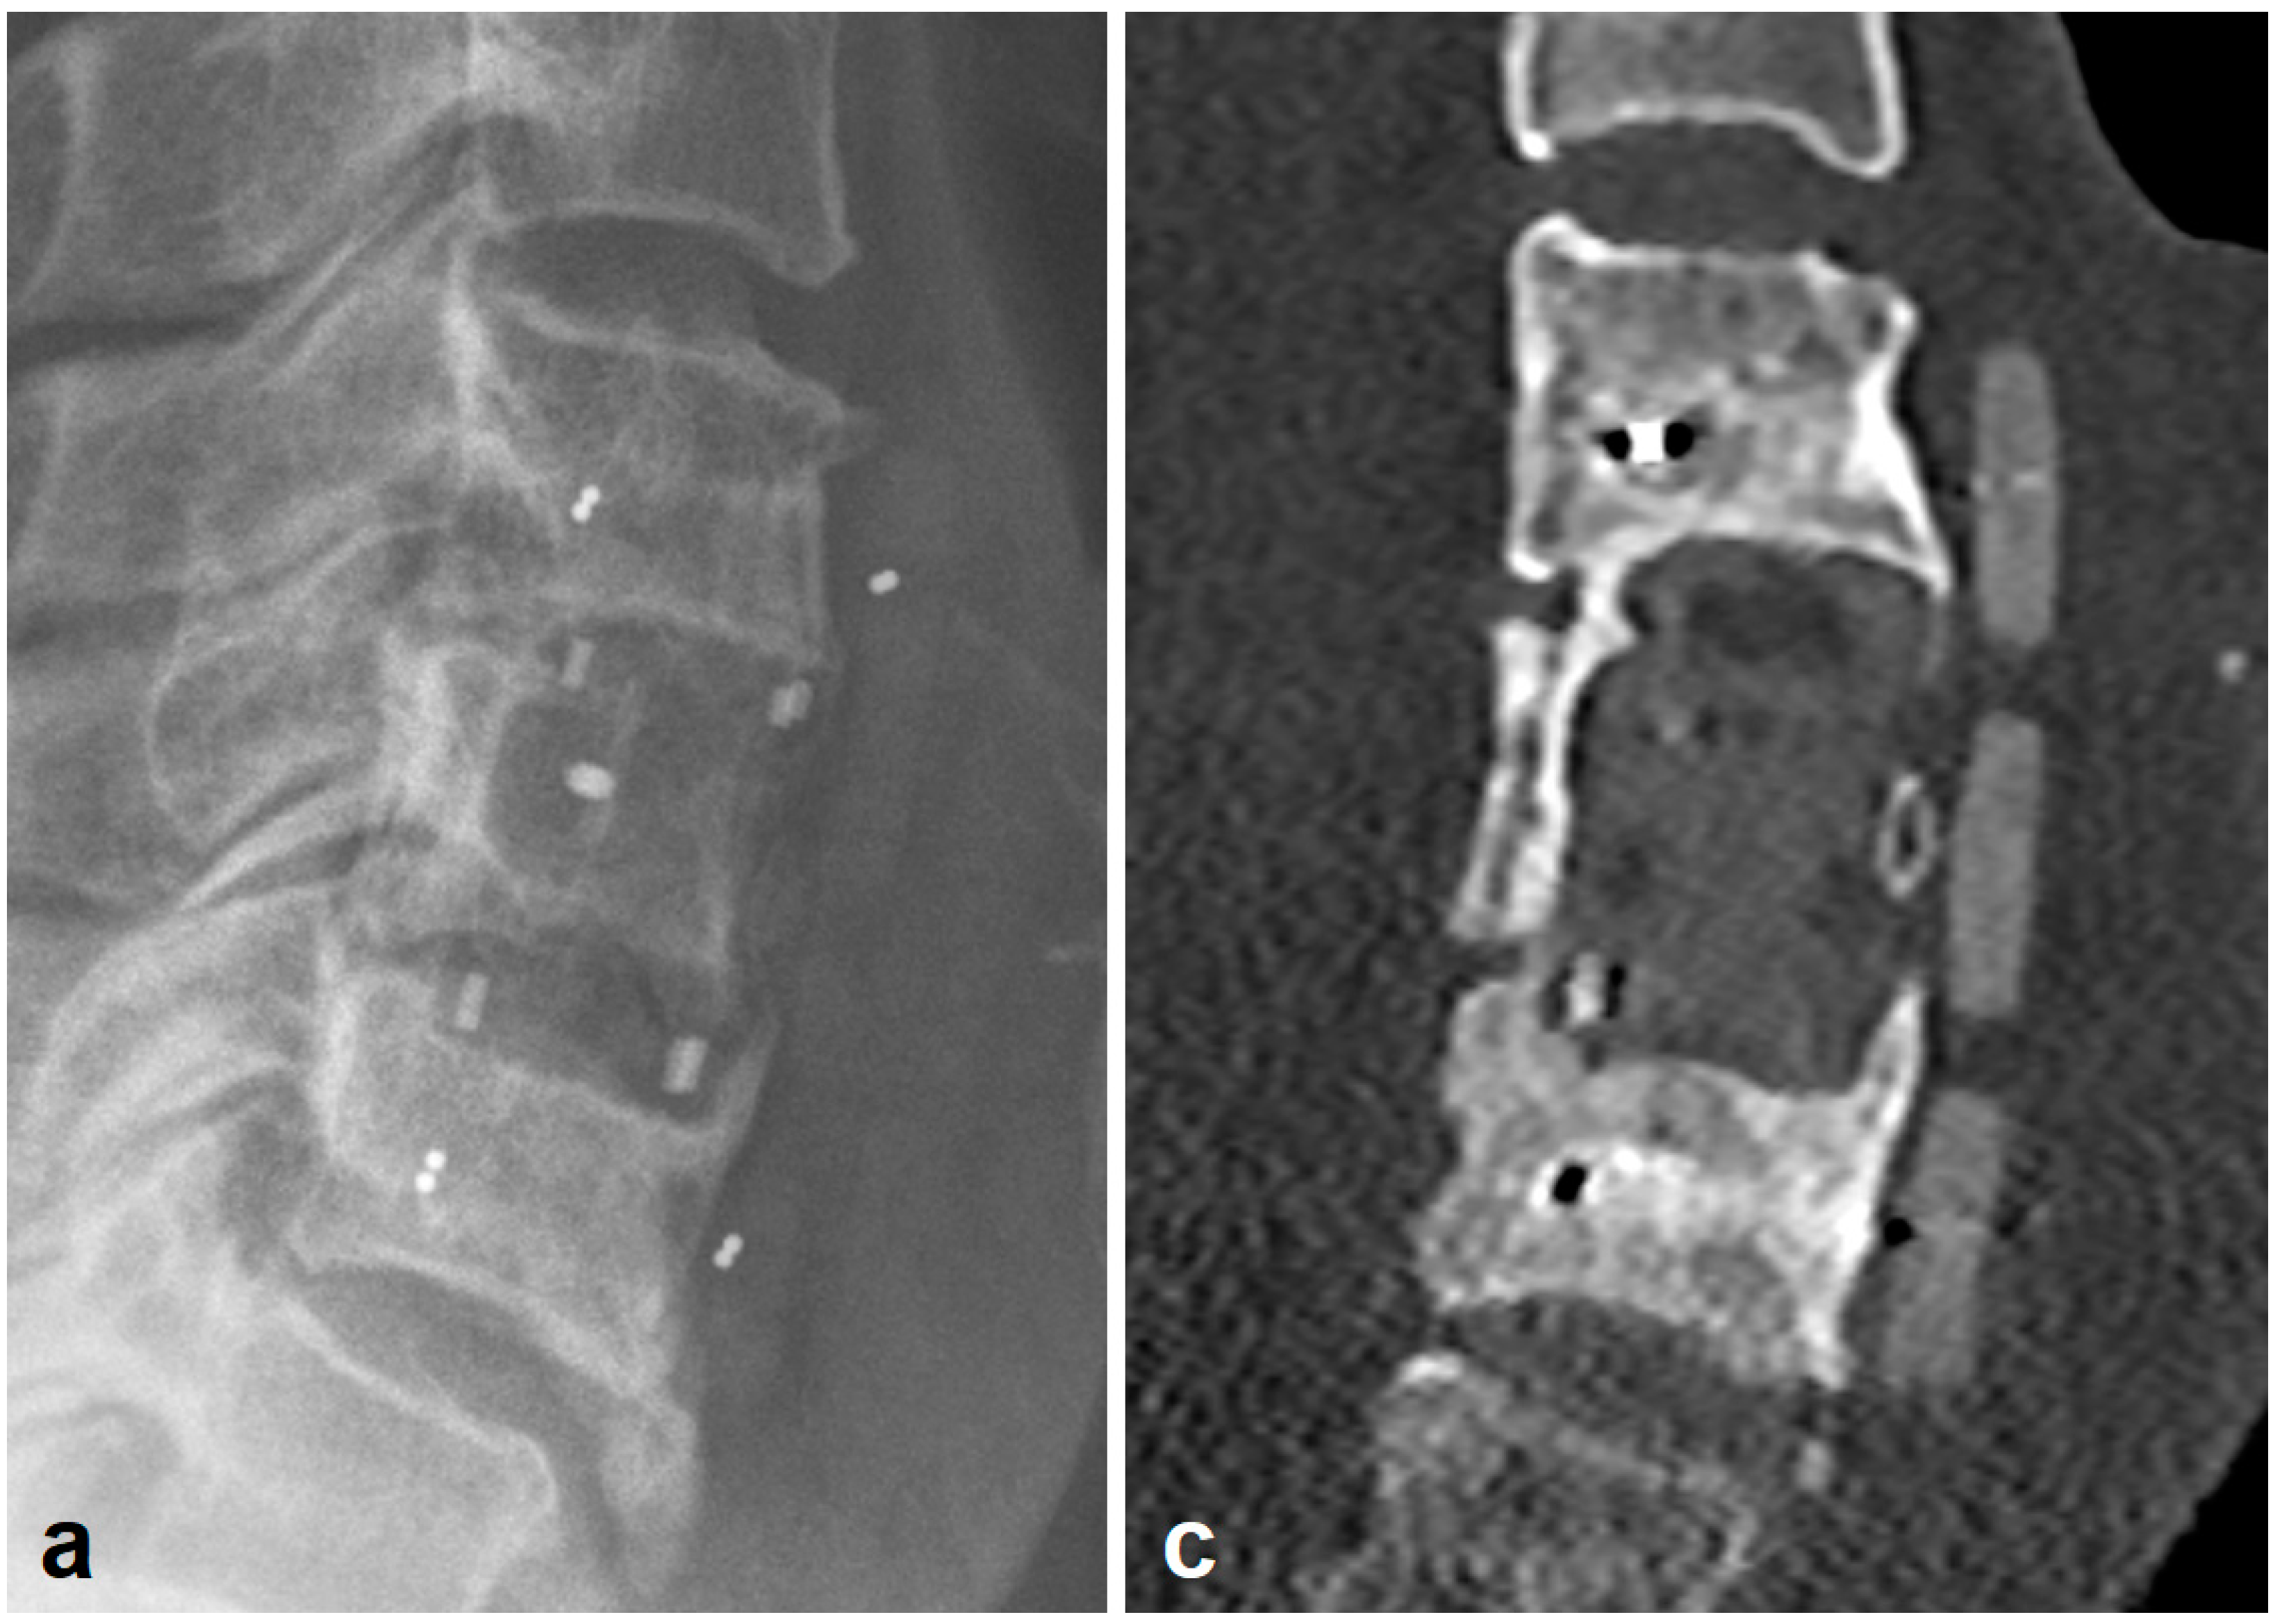

2.3. Radiologic Outcome

- Deml, M.C.; Sepulveda, C.A.M.; Albers, C.E.; Hoppe, S.; Bigdon, S.F.; Häckel, S.; Milavec, H.; Benneker, L.M. Anterior column reconstruction of the thoracolumbar spine with a new modular PEEK vertebral body replacement device: Retrospective clinical and radiologic cohort analysis of 48 cases with 1.7-years follow-up. Eur. Spine J. 2020, 29, 3194–3202. [Google Scholar] [CrossRef] [PubMed]

- Schnake, K.J.; Stavridis, S.I.; Kandziora, F. Five-year clinical and radiological results of combined anteroposterior stabilization of thoracolumbar fractures. J. Neurosurg. Spine 2014, 20, 497–504. [Google Scholar] [CrossRef] [PubMed]

- Eck, K.R.; Lenke, L.G.; Bridwell, K.H.; Gilula, L.A.; Lashgari, C.J.; Riew, K.D. Radiographic Assessment of Anterior Titanium Mesh Cages. J. Spinal Disord. 2000, 13, 501–509. [Google Scholar] [CrossRef] [PubMed]